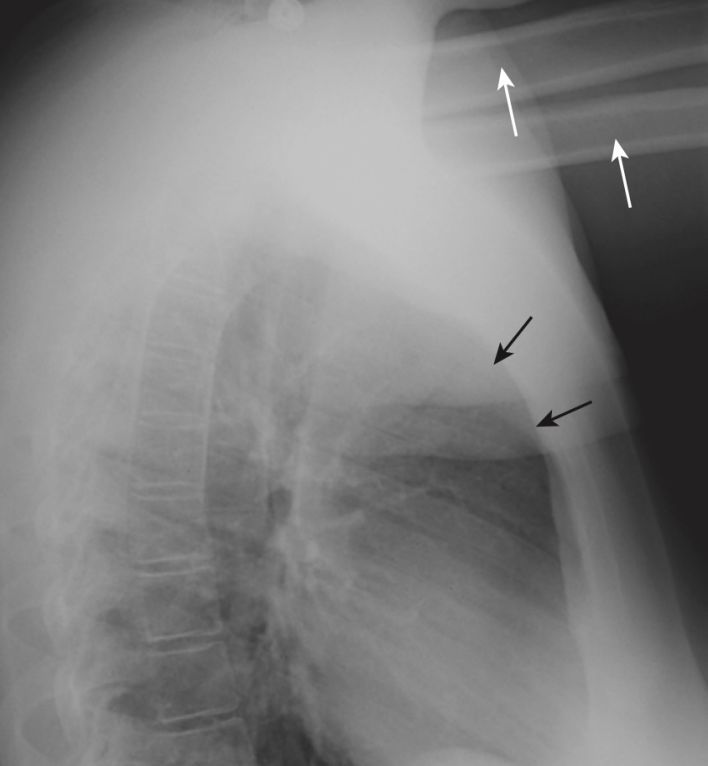

- Lưu ý Cạm bẫy: Hãy cẩn thận để không nhầm mô mềm của cánh tay của bệnh nhân chồng lên với “lấp đầy” khoảng trống. Mặc dù bệnh nhân được yêu cầu giữ hai tay qua đầu để bộc lộ ngực bên, nhưng nhiều bệnh nhân quá yếu không thể nâng cánh tay lên được.

- Giải pháp: Bạn sẽ có thể xác định cánh tay của bệnh nhân trên phim chụp X quang bằng cách phát hiện xương cánh tay (Hình 6).